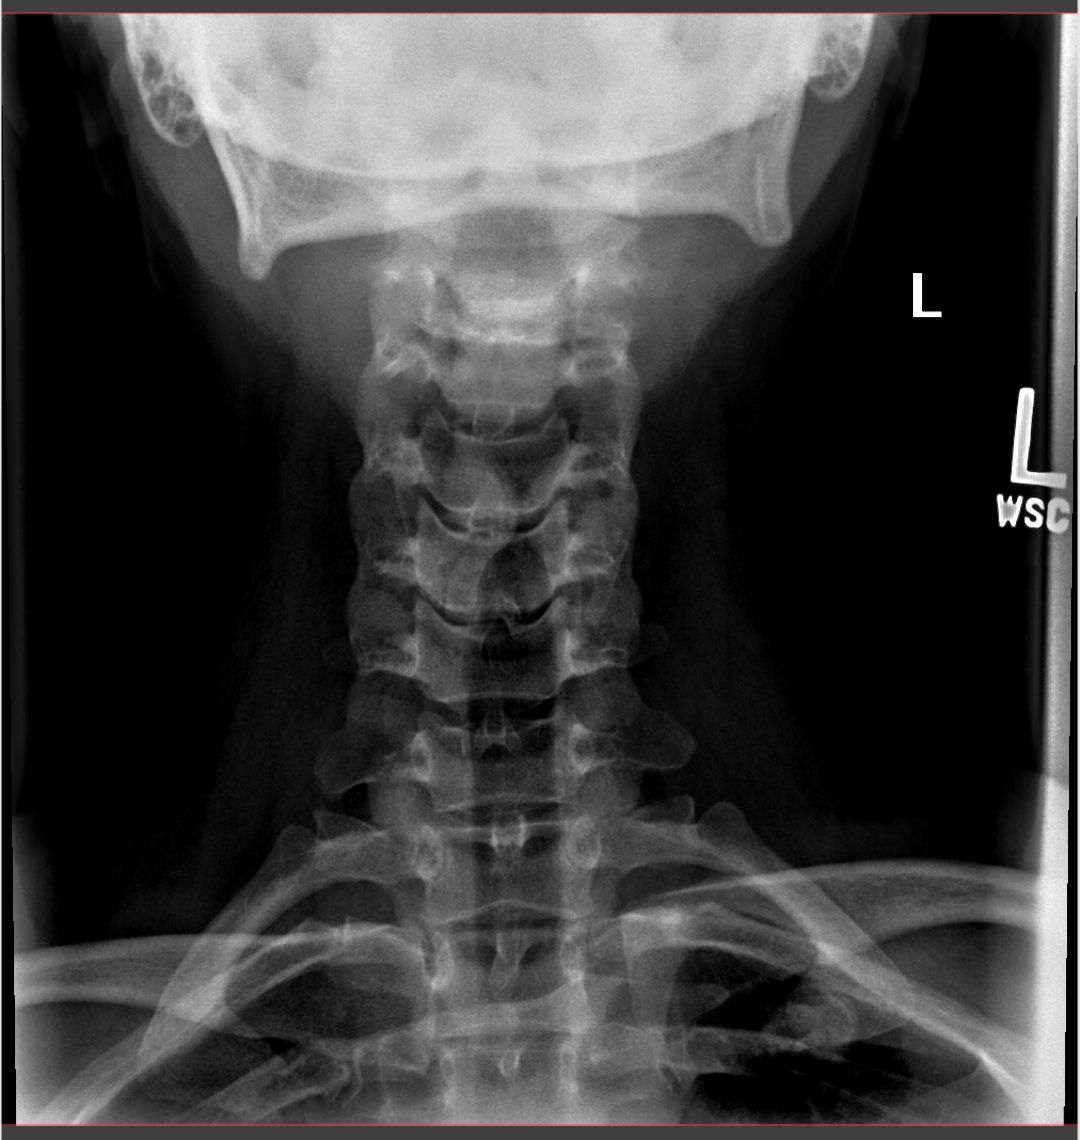

I was given a prescription for meds and had x-rays taken of my neck and spine – I felt silly when I had to get some of the x-rays with my mouth open wide.

My X-rays showed degenerative disc disease in my C-4 to C-5 and C-5 to C-6 spine area, with bone spurs and muscle spasms. No wonder my neck has been killing me lately.